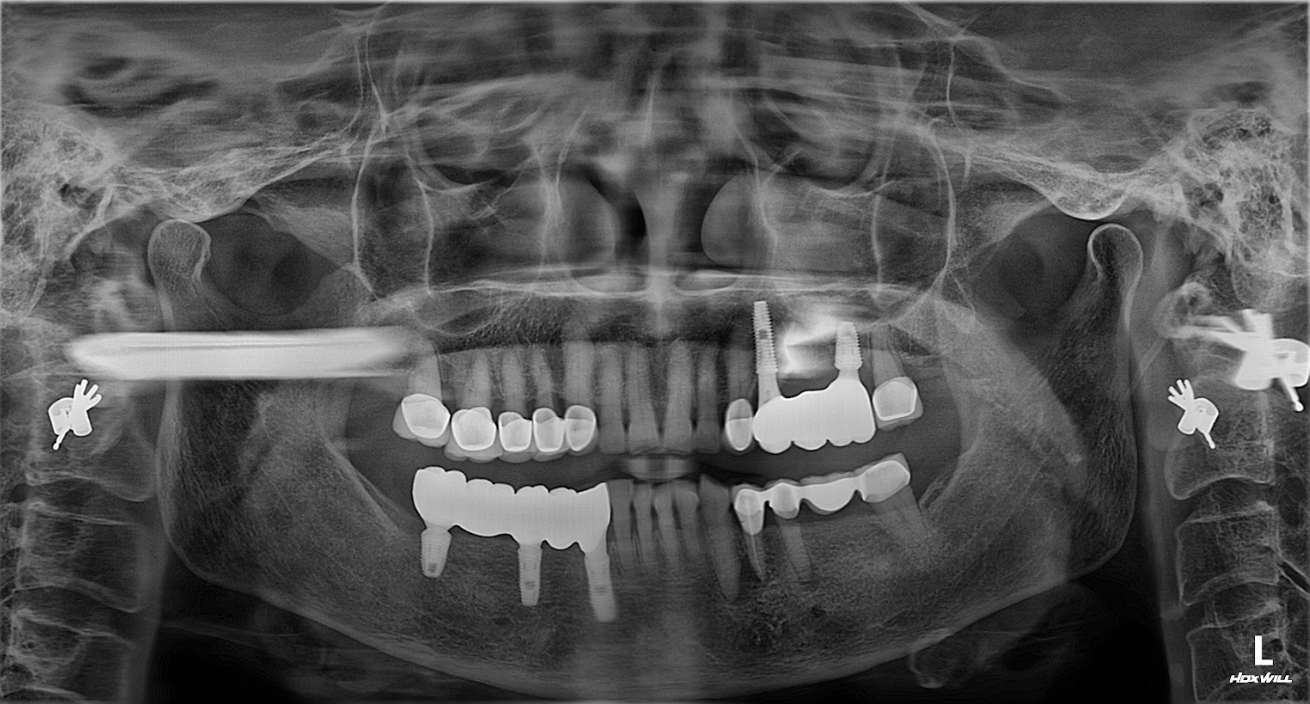

• Phim toàn cảnh (Panorex)

Giúp quan sát tổng thể 2 hàm, vị trí răng còn lại, xương và xoang.

→ Thường dùng trong bước khảo sát ban đầu.